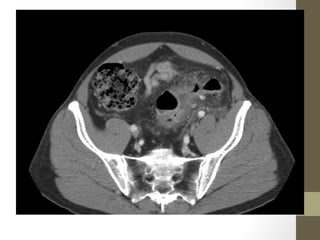

TOA

• 42.